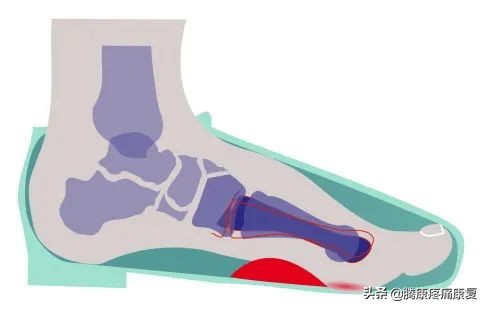

足部受力图

最好是在跖趾关节受到永久损伤之前,通过足部锻炼、固定夹板和手术治疗来固定大脚趾的位置。